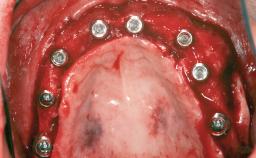

Ridge Preservation and Implant Placement for a Fixed Dental Prosthesis After a Car Accident

It is well known to clinicians that any removal of teeth will, over time, cause the dimensions of the alveolar ridge to be reduced by resorption of the bundle bone and by changes related to external modeling. This development is particularly evident in the crestal region with its thin buccal bone that consists of bundle bone almost entirely. The facial bone will rapidly resorb as blood supply from the periodontal ligament gets disrupted (Araújo and Lindhe 2005). There is no reason why traumatic tooth loss should not have the same consequences. It takes more than achieving implant osseointegration for a treatment outcome to be considered successful. No deficiency of bone or soft tissue is acceptable when an ideal esthetic outcome is the goal. Several articles (Sanz and coworkers 2011; Vignoletti and coworkers 2011) have reported on techniques of improving the alveolar ridge for implant treatment, notably focusing on protecting tissues from resorption.

# of Implants 4

Type of Implants One-Piece|Reduced-Diameter

Bone Augmentation Horizontal|Simultaneous|Sinus Floor Elevation|Staged